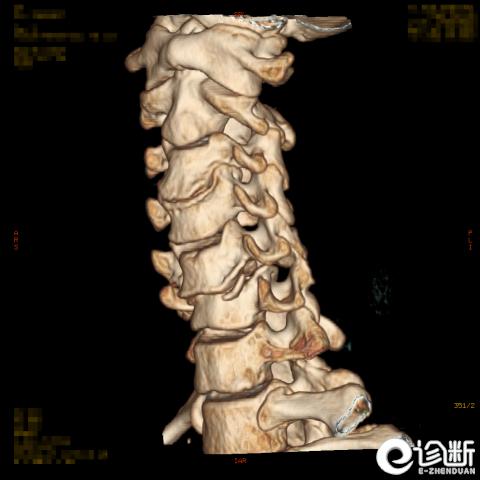

颈椎骨折

CT:显示椎管(骨折碎片可压迫椎管)

分型:

根据骨折的水平及位置:C1-Jeferson骨折:前后弓骨折

C1-侧块骨折

C2-Hangman骨折(峡部):Levine分型

C2齿突骨折1型、2型、3型

C3-7骨折:

棘突骨折(Clay shoveler骨折):C6,7,T1(C7最常见)